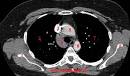

La thrombose de la veine cave suprieure est secondaire dans les trois quarts des cas un cancer du poumon, le plus souvent un CANCER. Syndrome de la veine cave suprieure pdia Le syndrome de la veine cave suprieure (SVC ou SCVCS ) est en gnral le rsultat de l obstruction partielle ou complte de la veine cave suprieure. Chirurgie de la veine cave suprieure La chirurgie de la veine cave suprieure se situe aux confins de la chirurgie thoracique et de. Thrombose veine cave inferieure spontane - Vulgaris Mdical. Il peut s agir d une invasion tumorale directe, d une compression externe ou d une thrombose.

Thrombose cave isole Thromboses de la veine cave infrieure tiologies particulires. mcanismes l origine du syndrome de la veine cave suprieure compression externe de la veine thrombose. ARS - Agences Rgionales de Sant: Formation : laposOutil PATHOS Formation l outil PATHOS EHPAD. Bouche daposextraction (collectif) - VMC et arateur - Chauffage.